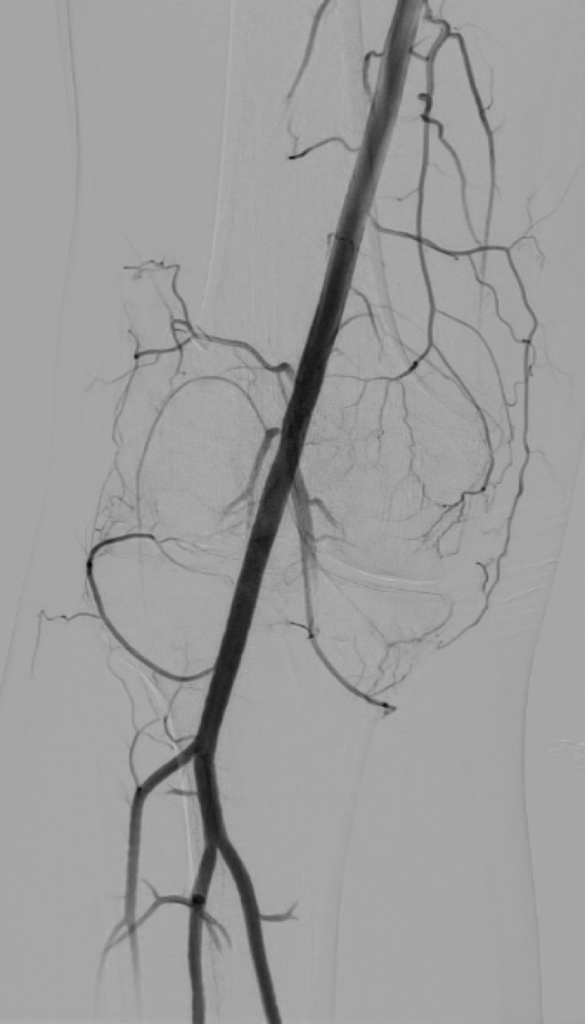

1. Accès vasculaire : Un cathéter est inséré au niveau de l'artère fémorale, au niveau de l'aine.

2. Navigation dans les artères : Le cathéter est guidé sous contrôle radiologique (souvent par fluoroscopie) jusqu'aux artères géniculées du genou.

3. Angiographie : Un produit de contraste est injecté pour obtenir des images détaillées des artères du genou et déterminer précisément les zones inflammatoires à emboliser.

Artériographie fémorale superficielle Artériographie supra sélective de l'artère géniculée inféro-médiale